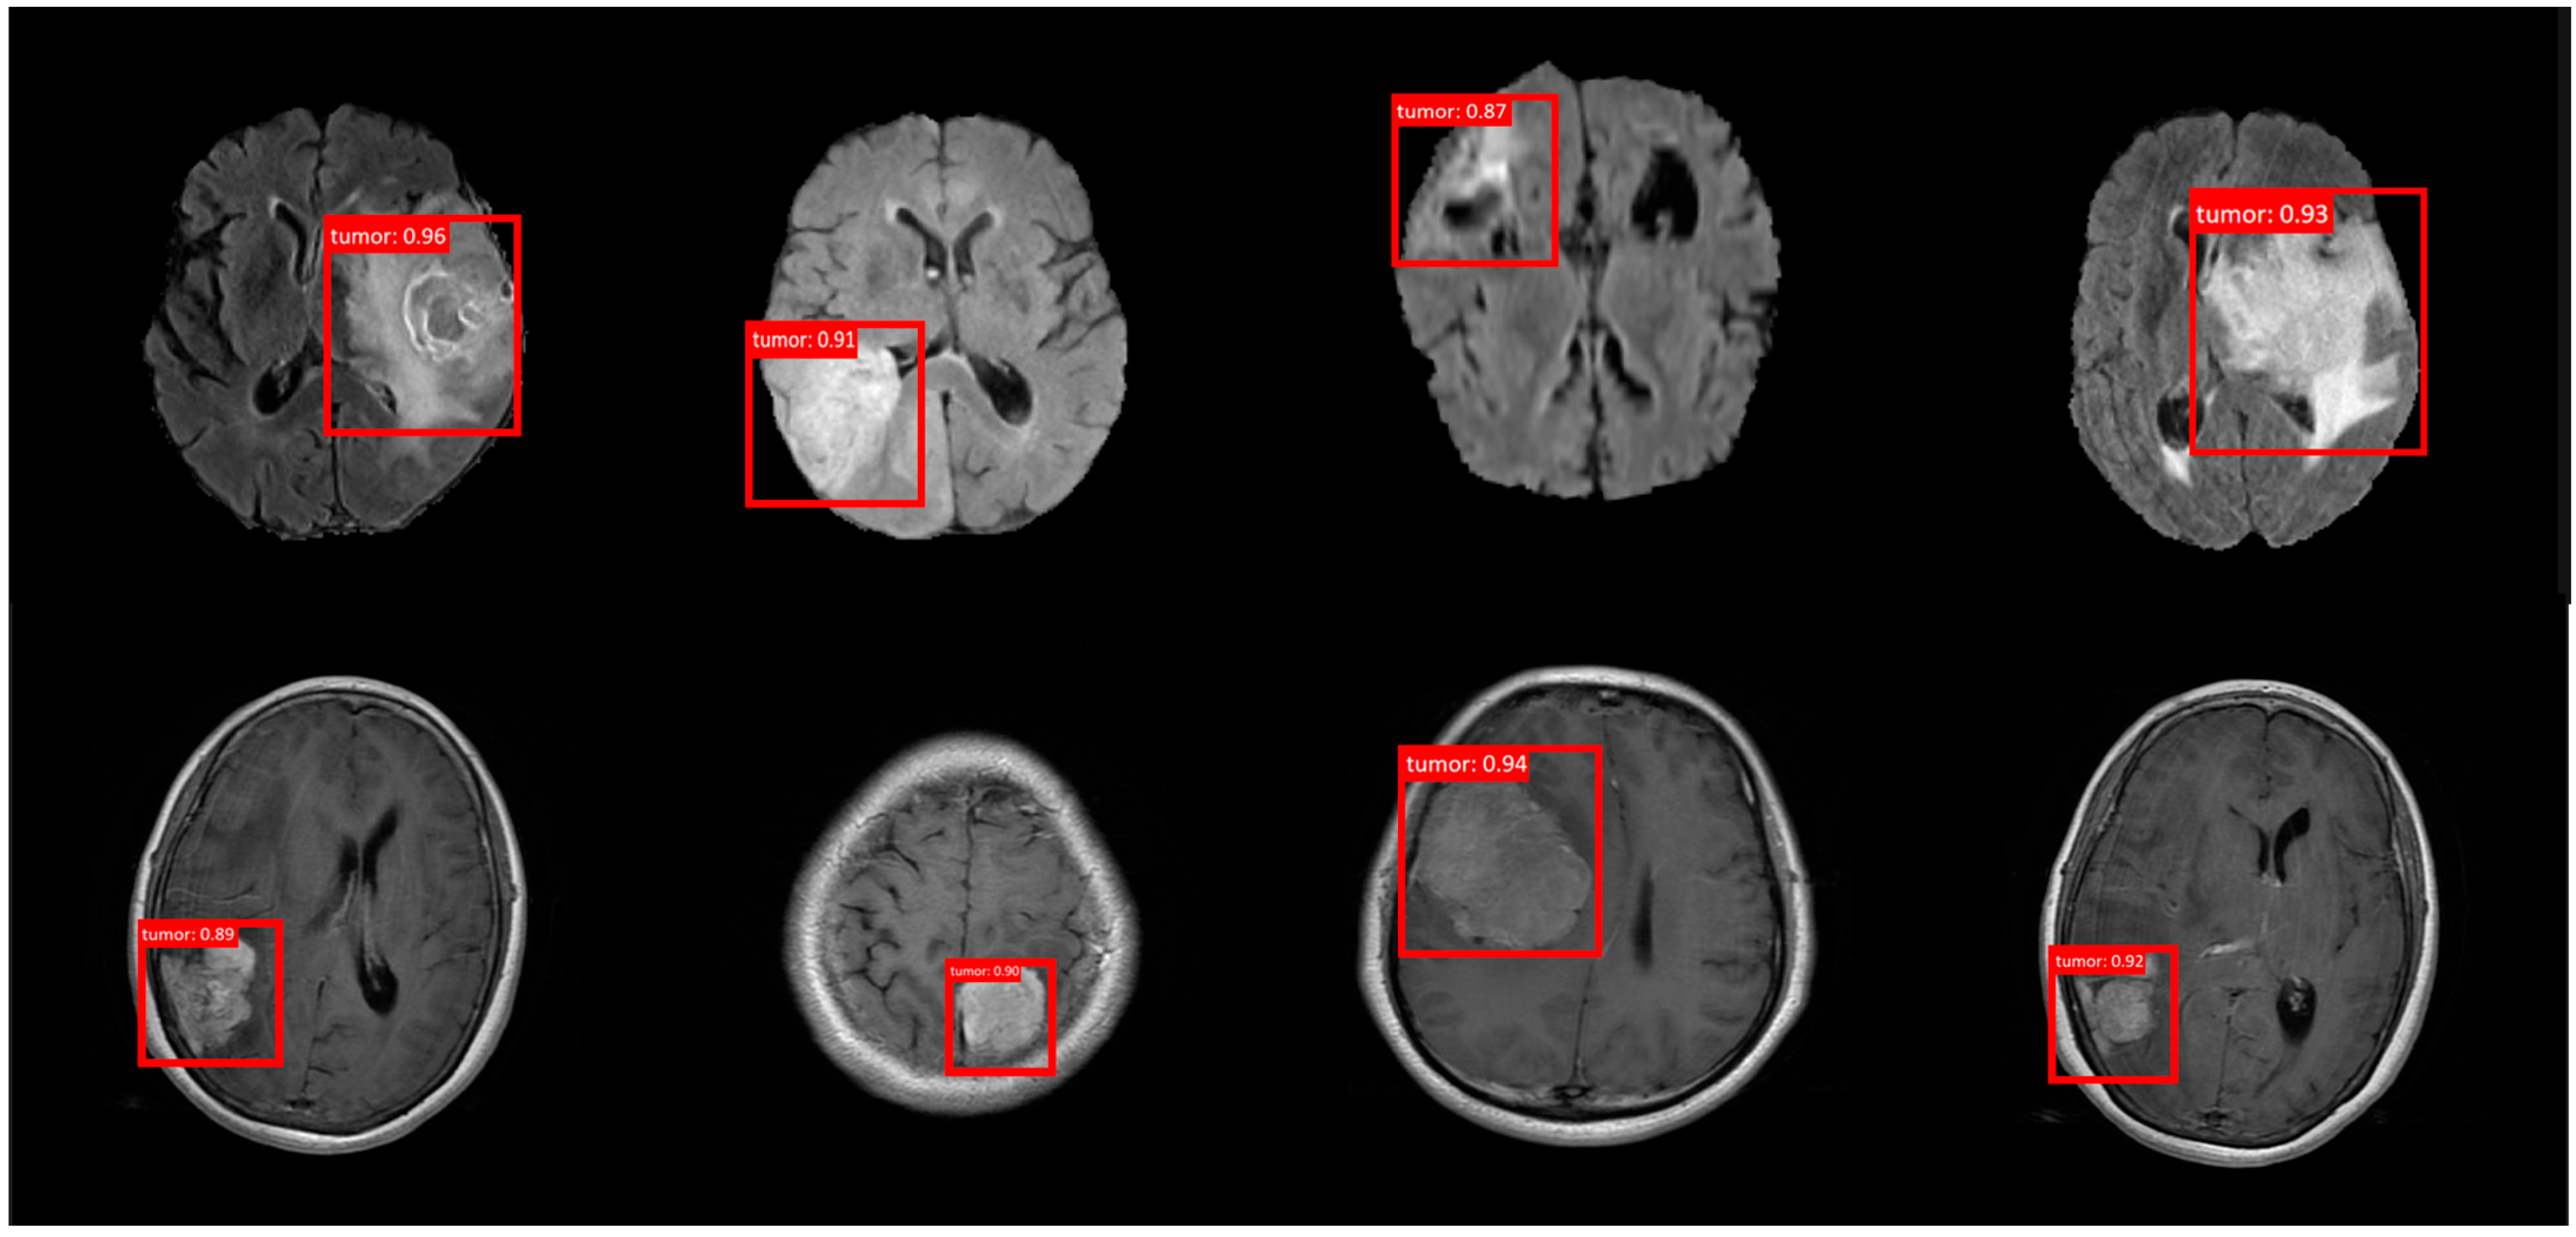

4.3. The Analyses of the Results and Comparison of the Baseline Models

| Model | Dataset | Input Shape | Params (M) | FLOPs (G) | AP | Epochs |

|---|---|---|---|---|---|---|

| Yolov5 | BraTS + ANDI | 240 × 240 | 7.2 | 9.6 | 0.816 | 300 |

| Yolov6 | BraTS + ANDI | 240 × 240 | 17.1 | 22.2 | 0.83 | 300 |

| Yolov7 | BraTS + ANDI | 240 × 240 | 34.9 | 45.7 | 0.82 | 300 |

| Yolov8 | BraTS + ANDI | 240 × 240 | 42.4 | 54.2 | 0.781 | 300 |

| Yolov9 | BraTS + ANDI | 240 × 240 | 44.2 | 57.8 | 0.842 | 300 |

| Yolov10 | BraTS + ANDI | 240 × 240 | 48.6 | 62.3 | 0.85 | 300 |

| Yolov11 | BraTS + ANDI | 240 × 240 | 52.3 | 67.1 | 0.858 | 300 |

| Baseline | BraTS + ANDI | 240 × 240 | 8.99 | 14.8 | 0.846 | 300 |

| RTMDet (Ours) | BraTS + ANDI | 240 × 240 | 6.76 | 9.65 | 0.969 | 300 |